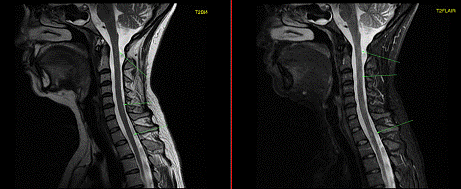

исследованиях этих областей оба метода являются конкурентными. В то же время в

изучении стволовой части головного мозга и всего спинного мозга, сердца и

сосудистых структур (в том числе головного мозга), конечностей (особенно

суставов), органов малого таза преимущество принадлежит МРТ. Вполне объяснимо

Наиболее часто в онкологической практике МРТ

необходима для дифференциальной диагностики первичных и вторичных опухолей

центральной нервной системы (ствол и спинной мозг), сердца и перикарда,

позвоночника.

МРТ центральной нервной системы

МРТ сердца МРТ желудка и кишечника